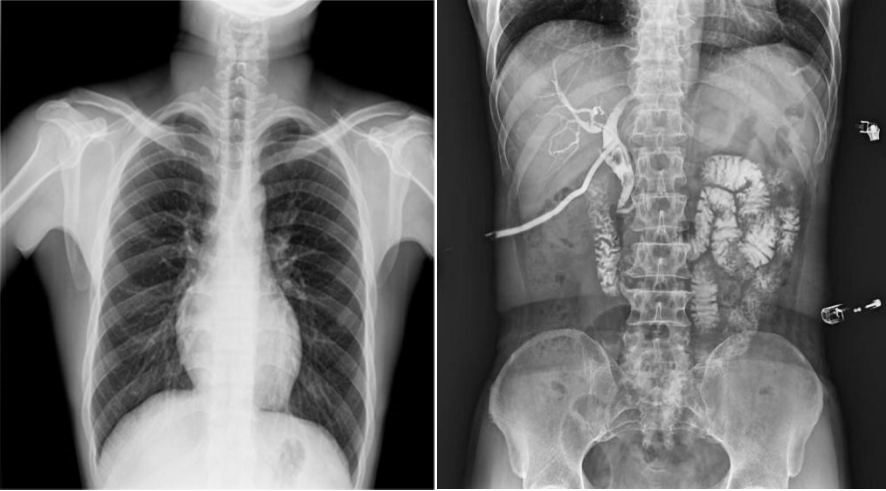

高幀動態平板,快速獲得高清影像。線性探測平面,圖像無畸變、無失真;17×17英寸超大視野,透視幅面大,一幅畫面即可覆蓋成年人的全胸全腹;30幀/s采集幀速,畫面流暢無卡頓;1800W高清像素點片,影像質量攀升新高度;并且能夠在毫秒級時間內進行動靜態影像切換,實時點片,快速捕捉病灶部位。